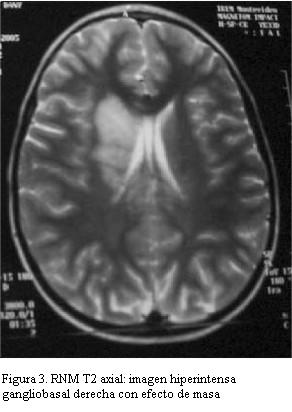

RNM: extensas lesiones hiperintensas en T2 y Flair gangliobasal externo e interno derecho incluyendo cápsula interna con ligero efecto de masa. Lesión de tálamo a izquierda y lóbulos temporales a nivel de los uncus del hipocampo bilateral y cerebelo. Lesiones a nivel de ambos pedúnculos cerebrales, protuberancia y sector anterior de bulbo. Angiorresonancia: gruesos troncos arteriales de territorio cerebral anterior, media y posterior permeables, menor visualización de ramas arteriales secundarias que aparecen adelgazadas (figuras 3 y 4).

La resonancia magnética nuclear es el examen de elección para confirmar estas alteraciones, revelando en el neuro-Behçet tres patrones característicos: una fase inicial en la que se evidencian focos de hiperintensidad en T2 a nivel de tronco cerebral, gangliobasal y hemisferios cerebrales; una fase intermedia con mayor inflamación que causaría edema y efecto de masa que puede regresar espontáneamente o con tratamiento inmunosupresor, pudiendo encontrar focos de microhemorragia con hiposeñal por los depósitos de hemosiderina, y finalmente en la fase crónica predominan imágenes de atrofia especialmente en tronco encefálico. El seguimiento neuroimagenológico evidencia regresión o desaparición de las lesiones parenquimatosas a largo plazo (meses a años) (19).